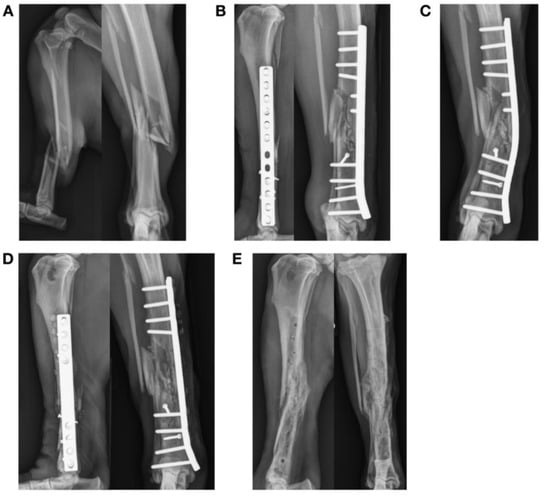

3.3. Plate Failure (11 Fractures)

| 14 | Y | Femur | Diaphyseal | Y | Y | 10 | 5 | 6 | 0.70 | 70.2 | 2.8 | 21.7 | 1.5/2.0 LCP | 0.79 | Lateral |

| 15 | N | Femur | Diaphyseal | Y | N | 9 | 5 | 6 | 0.67 | 73.2 | 3.0 | 17.7 | 1.5 mm straight plate stacked | 0.32 | Lateral |

| 16 | N | Femur | Diaphyseal | N | Y | 10 | 10 | 8 | 0.80 | 59.8 | 2.2 | 30.7 | 2.0 mm LC-DCP | 2.66 | Lateral |

| 17 | Y | Femur | Diaphyseal | N | Y | 9 | 10 | 8 | 1.00 | 84.5 | 8.8 | 10.0 | 2.0 mm LCP | 0.79 | Lateral |